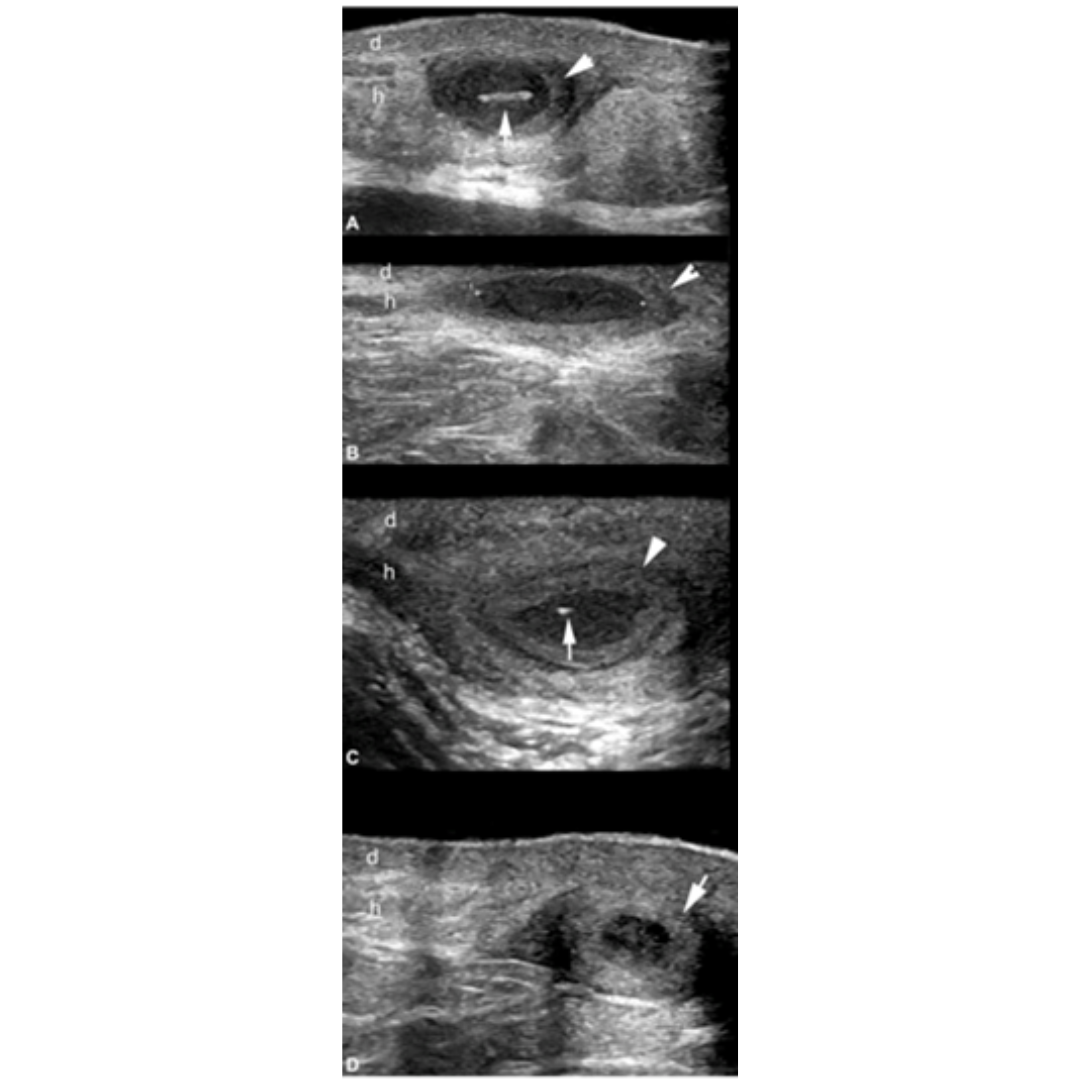

Figura 3: Imágenes de ecografía con apariencia variable de fistula. Se observan conexión de las fistulas con la parte inferior de los folículos pilosos dilatados y los fragmentos lineales hiperecogénicos de tractos pilosos dentro de la fistula.

Figura 4: Hidradenitis supurativa de presentación variable, colecciones de líquido dérmico e hipodérmico. El asterisco señala las colecciones y las puntas de flecha apuntando hacia arriba indican los fragmentos lineales hiperecogénicos de los tractos pilosos dentro de la colección. Las flechas apuntando hacia abajo indican las conexiones entre las colecciones de líquido con los folículos pilosos dérmicos ensanchados.